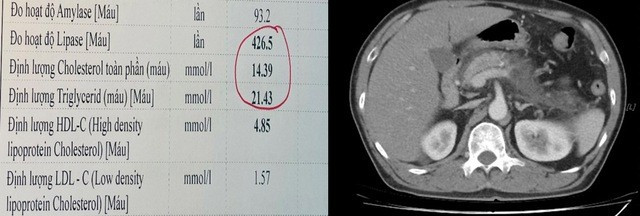

Kết quả xét nghiệm cho thấy men tụy và mỡ máu tăng rất cao, gấp khoảng 12 lần giới hạn bình thường (Cholesterol 14,3 mmol/L, Triglycerid 21,43 mmol/L). Hình ảnh chụp CT ổ bụng ghi nhận tổn thương tụy nặng, thâm nhiễm và có tụ dịch quanh tuyến tụy, biểu hiện của viêm tụy cấp mức độ nặng, thâm nhiễm kèm tụ dịch xung quanh.

Kết quả xét nghiệm mỡ máu tăng rất cao (trái) và hình ảnh tổn thương viêm tụy cấp mức độ nặng trên phim CT ổ bụng của bệnh nhân (phải). Ảnh SKĐS